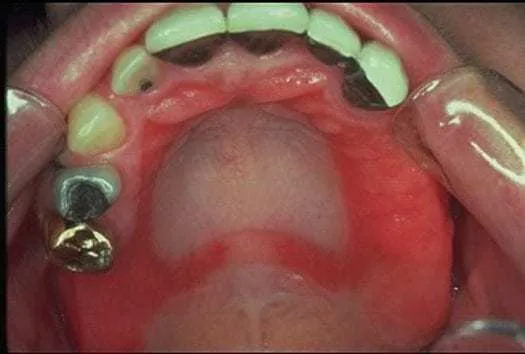

Poza subiektywnymi odczuciami, alergia na nikiel może manifestować się również widocznymi zmianami w jamie ustnej. Podczas badania stomatologicznego możemy zaobserwować:- Zaczerwienienie, obrzęk i bolesność dziąseł, podniebienia, języka lub wewnętrznej strony policzków. Jest to objaw zapalenia błony śluzowej, często mylony z innymi przyczynami.

- Pojawianie się bolesnych nadżerek i aft, które nawracają i trudno się goją, szczególnie w miejscach kontaktu z metalowym elementem.

- Obrzęk warg i języka, który może być na tyle nasilony, że utrudnia mówienie i połykanie.

- Zapalenie kącików ust (zajady), czyli pękanie i stany zapalne w kącikach warg, które są często przewlekłe i oporne na leczenie.